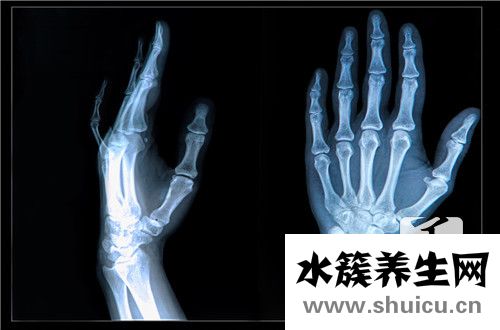

橈骨遠(yuǎn)端骨折非常常見(jiàn),約占平時(shí)骨折的1/10。多見(jiàn)于老年婦女,青壯年發(fā)生均為外傷暴力較大者。骨折發(fā)生在橈骨遠(yuǎn)端2~3cm范圍內(nèi)。常伴橈腕關(guān)節(jié)及下尺橈關(guān)節(jié)的損壞。

腕部腫脹、壓痛明顯,手和腕部活動(dòng)受限。伸直型骨折有典型的餐叉狀和槍刺樣畸形,尺橈骨莖突在同一平面,直尺試驗(yàn)陽(yáng)性。屈曲型骨折畸形與伸直型相反。注意正中神經(jīng)有無(wú)損傷。